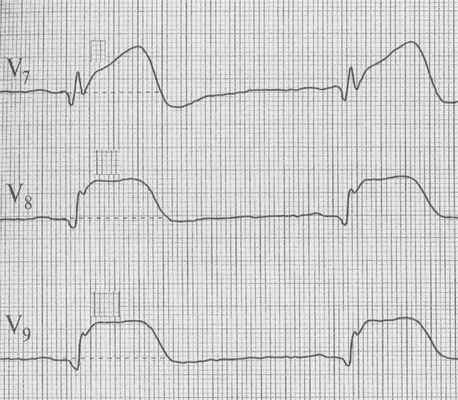

8.6.2.2.Инфаркт миокарда задней стенки левого желудочка (задне-базальный ИМ) обусловлен окклюзией задней нисходящей артерии (ПКА) или огибающей артерии (ЛКА), рисунок 138.

Отведения в которых определяются характерные ЭКГ признаки: V7-V9.

Реципрокные изменения определяются в отведениях: V1-V4.

Рис. 138. ЭКГ при заднем инфаркте миокарда.

Элевация сегмента ST V7-V9, реципрокная депрессия сегмента ST V1-V4, увеличение амплитуды зубца R V1-V2.